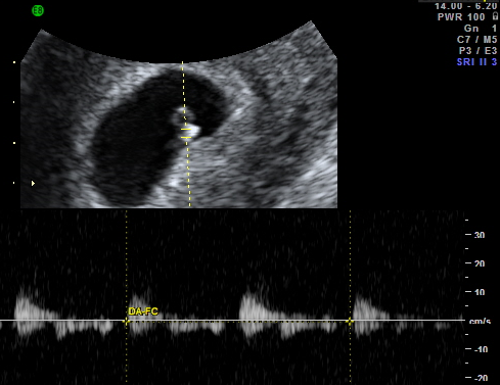

Ecografía Doppler

La ecografía Doppler permite evaluar la circulación sanguínea en el feto y detectar posibles problemas de flujo, como la restricción del crecimiento fetal o la preeclampsia. Los cambios en los patrones de flujo sanguíneo pueden indicar un riesgo para el bienestar del bebé.